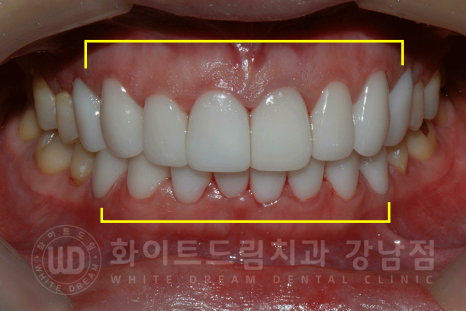

동일 인물이며, 동일 환경에서 촬영되었습니다. /강남역 앞니라미네이트

총 치료 기간 : 23.06.08 - 23.06.16

동일 인물이며, 동일 환경에서 촬영되었습니다.